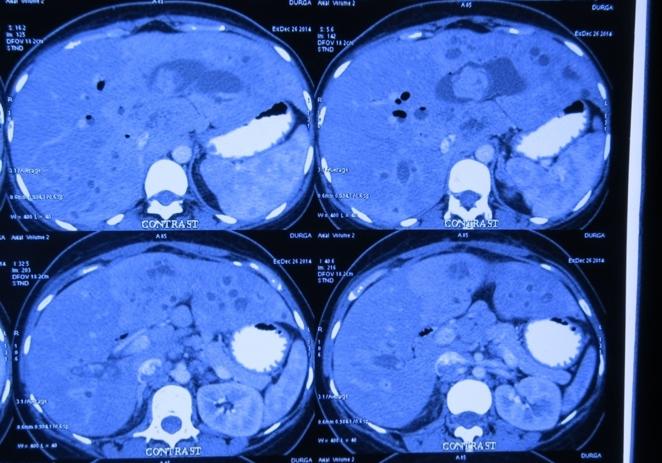

Recurrent pyogenic cholangitis (RPC) - 67 yr old Bangladeshi lady presented with recurrent episodes of jaundice, fever and pain for past 1 year

Interesting images: Recurrent pyogenic cholangitis (RPC) 67 yr old Bangladeshi lady presented with recurrent episodes of jaundice fever and pain for past 1 year. MRCP and CT scan showed left duct stricture with left sided IHBRD and CBD stones and atrophy of left lateral segment. As she 4 duct was also involved we did a left hepatectomy with hepaticoduodenostomy . Reccurant pyogenic cholangitis is a disease charecterised by multiple instances of biliary bacterial infection, hepatic abcesses , multiple stricturing of bile ducts with pigment stone formation in the intrahepatic and extrahepatic biliary tree. This can cause reccurant episodes of cholangitis, chronic illness ultimately leading to liver failure. It is more common in the far east population. Management includes long term biiary drainage with liver resections for segmental disease and liver transplantation in patients with end stage liver failure . The last CT scan shows another CT scan another similar patient with huge intrahepatic stones and abscesses managed successfully by surgery and long term PTBD.